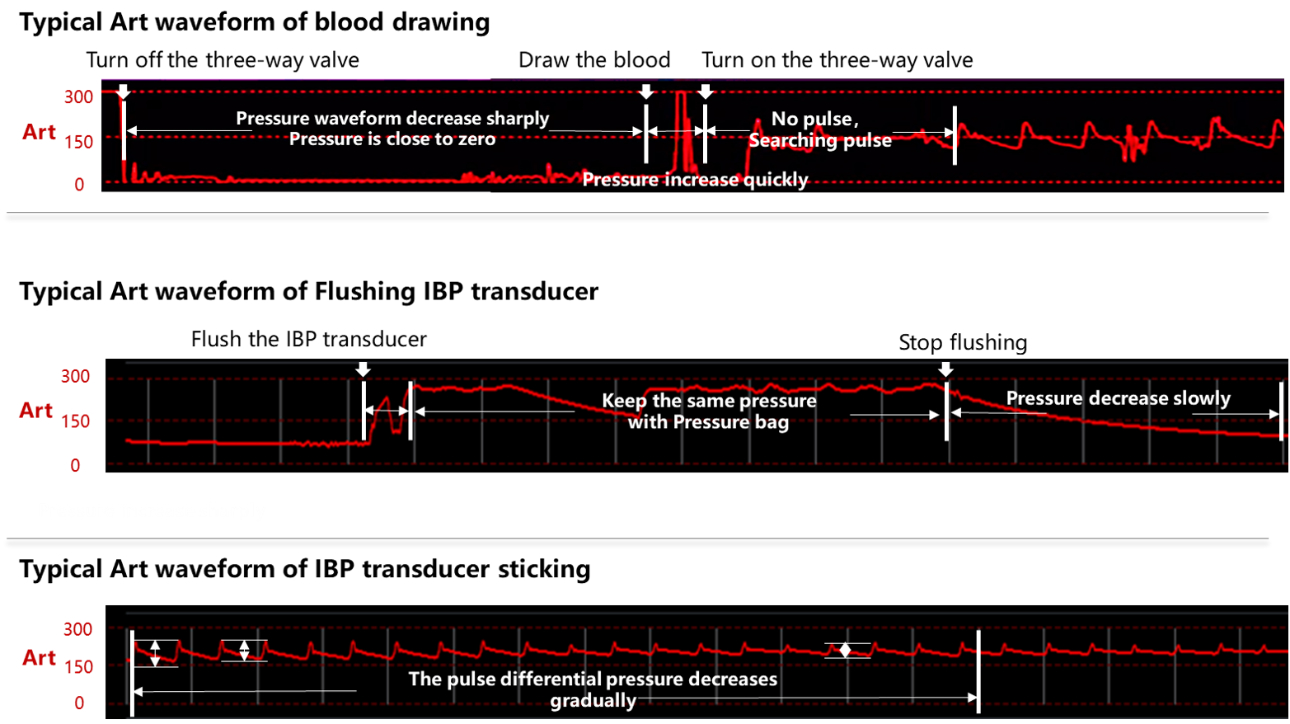

The vital signs trend table (as shown in Figure 5) shows that the patient experienced multiple dramatic spikes and drops of IBP after admission. Since IBP monitoring is easilyaffected by artificial factors, including blood drawing, tube flushing and bending, it is necessary to exclude the IBP interference and analysis patientŌĆÖ s blood pressure fluctuations, after confirming that it is not caused by interference, they reviewed all the vital signs again and found that multiple over-limit IBP alarms existed in a short period of time.

Doctors checked the full disclosure wave- forms of ECG, SPO2 and IBP, confirming that the sudden deterioration IBP were real phenomenon and happened to this patient. and also the abnormal IBP fluctuations could appear even though there were no adjustment of vasoactive agent and bedside manipulation stimulation.

Influence of different operations on the shape of the blood pressure waveform